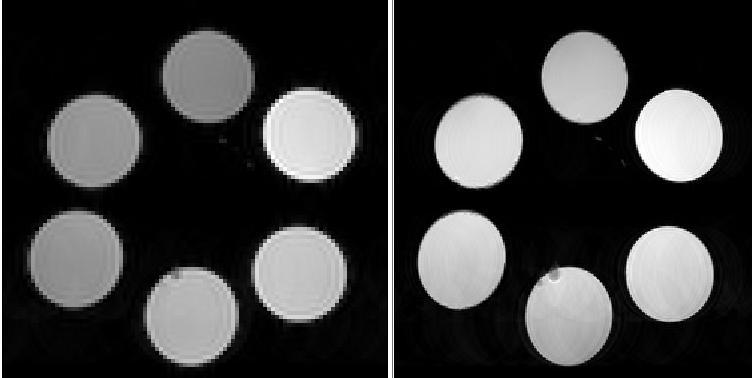

A collaboration with the imaging facility at Fred Hutch Cancer Center has demonstrated that py-me-glucoverdazyl is an effective T1w contrast agent

Preliminary in vivo MRI Studies

Contrast enhancement was observed in the left kidney (with longer retention than the ocglucoverdazyl) and the bladder We also have data that indicates that our compound is absorbed by the pancreas While we observed no noticeable ill-effects on the mouse, we will be examining the vital organs using the Fred Hutch pathology facilities